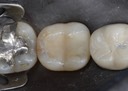

Joe Cha #20 finish